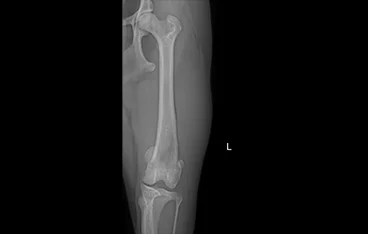

• PLATE

• PLATE 수술 전

PLATE 수술 후